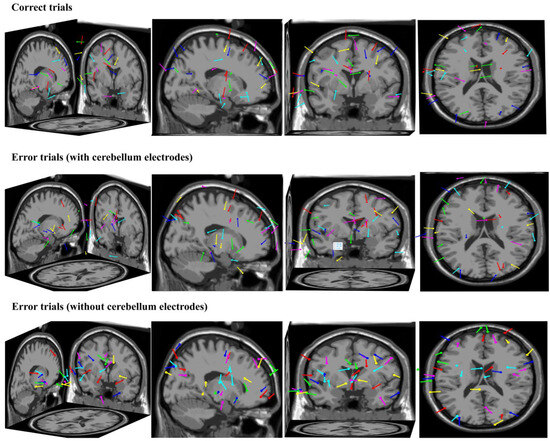

Identification and Verification of Error-Related Potentials Based on Cerebellar Targets

The error-related potential (ErrP) is a weak explicit representation of the human brain for individual wrong behaviors. Previously, ErrP-related research usually focused on the design of automatic correction and the error correction mechanisms of high-risk pipeline-type judgment systems. Mounting evidence suggests that the [...] Read more.

The error-related potential (ErrP) is a weak explicit representation of the human brain for individual wrong behaviors. Previously, ErrP-related research usually focused on the design of automatic correction and the error correction mechanisms of high-risk pipeline-type judgment systems. Mounting evidence suggests that the cerebellum plays an important role in various cognitive processes. Thus, this study introduced cerebellar information to enhance the online classification effect of error-related potentials. We introduced cerebellar regional characteristics and improved discriminative canonical pattern matching (DCPM) in terms of data training and model building. In addition, this study focused on the application value and significance of cerebellar error-related potential characterization in the selection of excellent ErrP-BCI subjects (brain–computer interface). Here, we studied a specific ErrP, the so-called feedback ErrP. Thirty participants participated in this study. The comparative experiments showed that the improved DCPM classification algorithm proposed in this paper improved the balance accuracy by approximately 5–10% compared with the original algorithm. In addition, a correlation analysis was conducted between the error-related potential indicators of each brain region and the classification effect of feedback ErrP-BCI data, and the Fisher coefficient of the cerebellar region was determined as the quantitative screening index of the subjects. The screened subjects were superior to other subjects in the performance of the classification algorithm, and the performance of the classification algorithm was improved by up to 10%. Full article